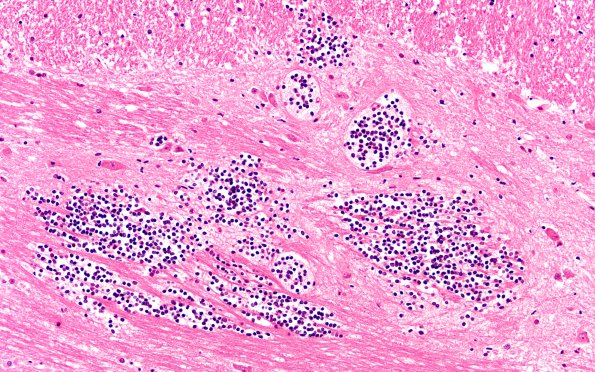

2B3 Hemorrhage (Case 2) 20X

2B3-6 The leukemic nodules consist of solid aggregates of immature neoplastic granulocytes. (H&E)